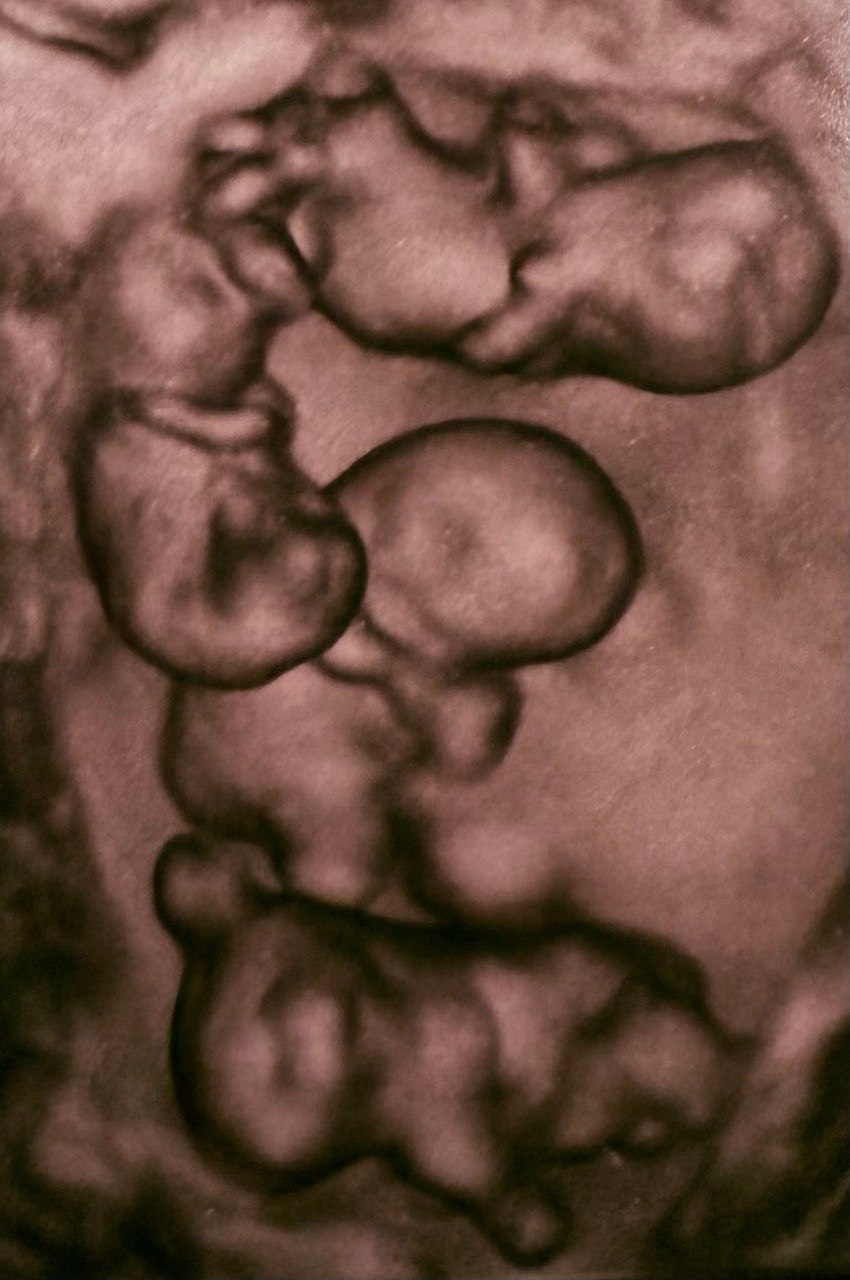

В Петербурге женщина родила сразу четырех девочек, причем все они — однояйцевые близнецы

Между прочим, это первый в России случай однояйцевой четверни. Вероятность таких родов один на 15,5 млн. Радостной новостью поделился один из профессоров, который курировал беременность россиянки.

Малышки родились недоношенными посредством кесарева сечения на 32 неделе. Вес девочек составил 1400, 1570, 1640 и 1360 граммов, рост — 38, 41, 41 и 37 см соответственно. Для такого раннего срока показатели считаются хорошими.

Всего в мире насчитывается около 15 идентичных четверняшек, причём 10 из них — девочки.